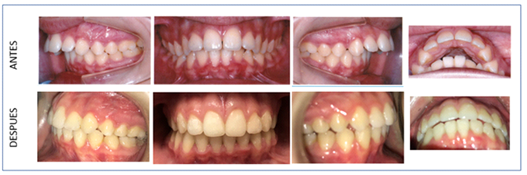

Patient MR

Female patient 13 years and 9 months old. Carpal radiography was performed to know in what stage of growth she was in order to decide the treatment plan (Figure 5). The patient was in the 5th stage of skeletal maturation so it was decided to place twin blocks. She was in the time limit for this technique. But in the eventuality of leaving her for surgery, it was preferred to try this device.

The intraoral photos show the great change in the patient. There is a decrease in the overjet, class 1 left canine and a slight class II right. He used the twin blocks day and night, only removing them for feeding and hygiene for 12 months. After treatment with twin blocks, orthodontics was performed to correct the slight anteroinferior crowding and to correct dental midlines. Fixed lower and removable upper containments were made. The total treatment period was 2 years (Figure 8).